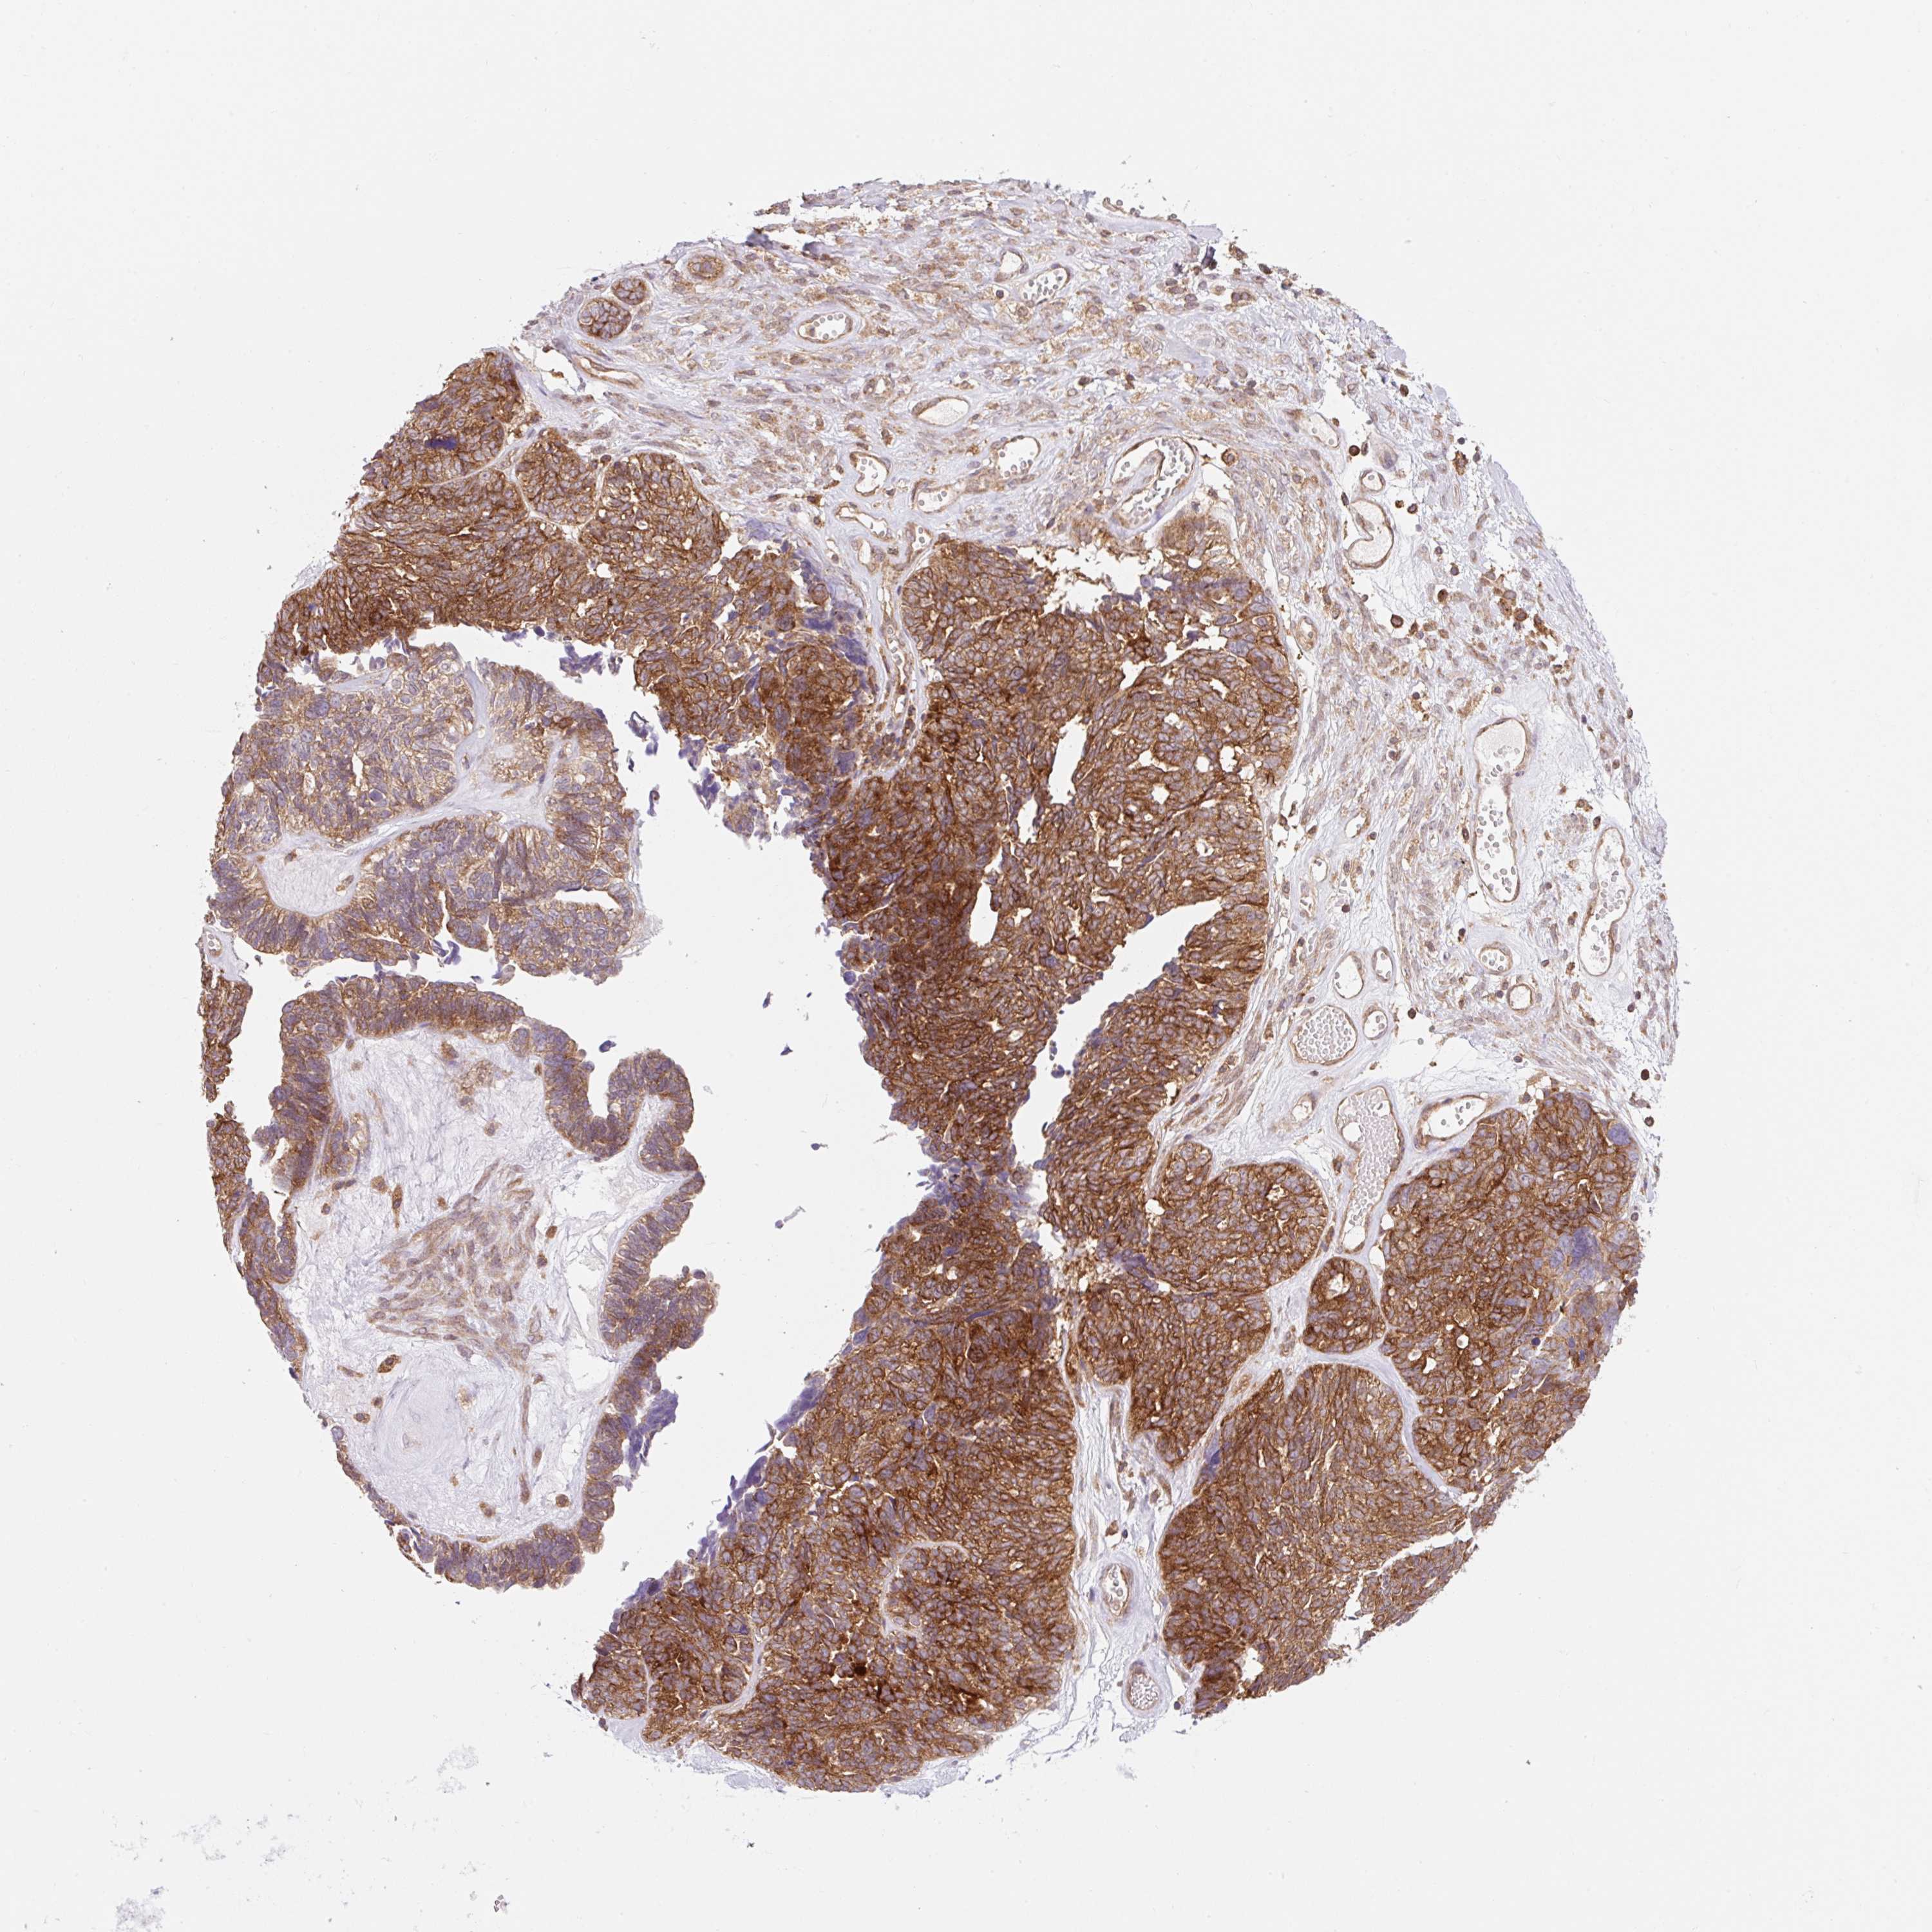

OVARIAN CANCER - Protein expressioni

A mouse-over function shows sample information and annotation data. Click on an image to view it in a full screen mode. Samples can be filtered based on level of antibody staining by selecting one or several of the following categories: high, medium, low and not detected. The assay and annotation is described here.

Note that samples used for immunohistochemistry by the Human Protein Atlas do not correspond to samples in the TCGA dataset.

Antibody stainingi

Antibody staining in the annotated cell types in the current human tissue is reported as not detected, low, medium, or high, based on conventional immunohistochemistry profiling in selected tissues. This score is based on the combination of the staining intensity and fraction of stained cells.

Each image is clickable and will lead to virtual microscopy that enables deeper exploration of all samples and also displays staining intensity scores, fraction scores and subcellular localization as well as patient and tissue information for each sample.

Antibody CAB034411

Cystadenocarcinoma, serous, NOS

Carcinoma, endometroid

Cystadenocarcinoma, mucinous, NOS

Carcinoma, NOS